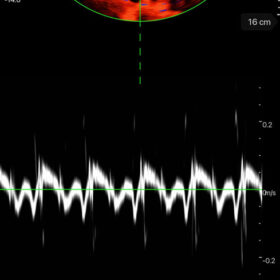

Mindray I3P WiFi Probe Image Gallery and Videos

Display mode: B, B/M, and Color, PW, PDI